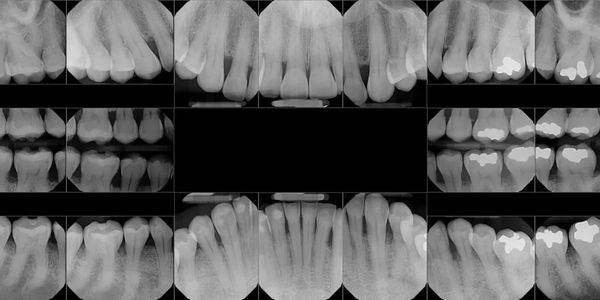

Your dental professional may use one or more different types of dental x-rays in order to properly assess and diagnose an issue.

Most dental x-rays are smaller in size and provide a close-up view of the teeth. These type of x-rays are referred to as bitewing x-rays and periapical x-rays. Our office uses digital x-rays which reduce radiation exposure. Dental x-rays are necessary to help diagnose things such as decay, abscesses, gum disease, wisdom tooth issues, or anything not visible under the gums. We follow strict x-ray guidelines in order to reduce exposure, and use protective lead lined aprons with thyroid collars and modern digital x-ray equipment.

Another important type of dental x-ray is called a Panorex image. This type of image gives an overall view of the mouth and supporting structures. These dental x-rays are helpful when monitoring the eruption of teeth into the mouth, especially wisdom teeth. They are helpful when showing the position of teeth in relation to each other and to dental nerves in the mouth as well. These are helpful when certain teeth need to be extracted.